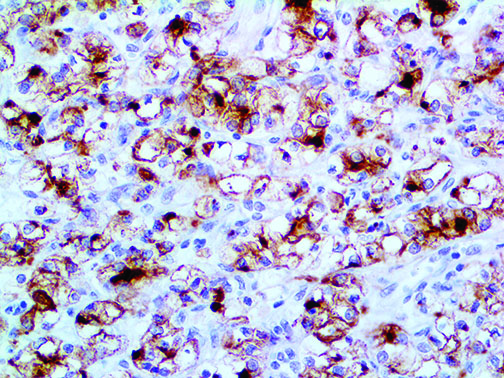

It is the ICU physician who is most likely to witness one of the deadliest manifestations of the abnormal immunological response, the cytokine storm syndrome (CSS). This response is also referred to by some as the cytokine release syndrome (CRS). CSS is characterized by continuous activation and expansion of macrophage and lymphocyte populations, which secrete large amounts of cytokines, causing the cytokine storm. This massive cytokine release is akin to hemophagocytic lymphohistiocytosis (HLH) disease, a syndrome characterized by initial unchecked and persistent activation of cytotoxic T lymphocytes and NK cells.

Clinical and laboratory manifestations of HLH include fever, enlarged liver and/or spleen, neurologic dysfunction, coagulopathy, liver dysfunction, cytopenias (i.e., low levels of erythrocytes, leukocytes, and/or platelets), hypertriglyceridemia, hyperferritinemia, hemophagocytosis, and eventually diminished NK cell activity as the immune system becomes progressively paralyzed. HLH can be familial (primary HLH) or secondary to another disease process (sHLH), such as rheumatic disease, in which it is referred to as macrophage activation syndrome (MAS, characterized by elevated ferritin).